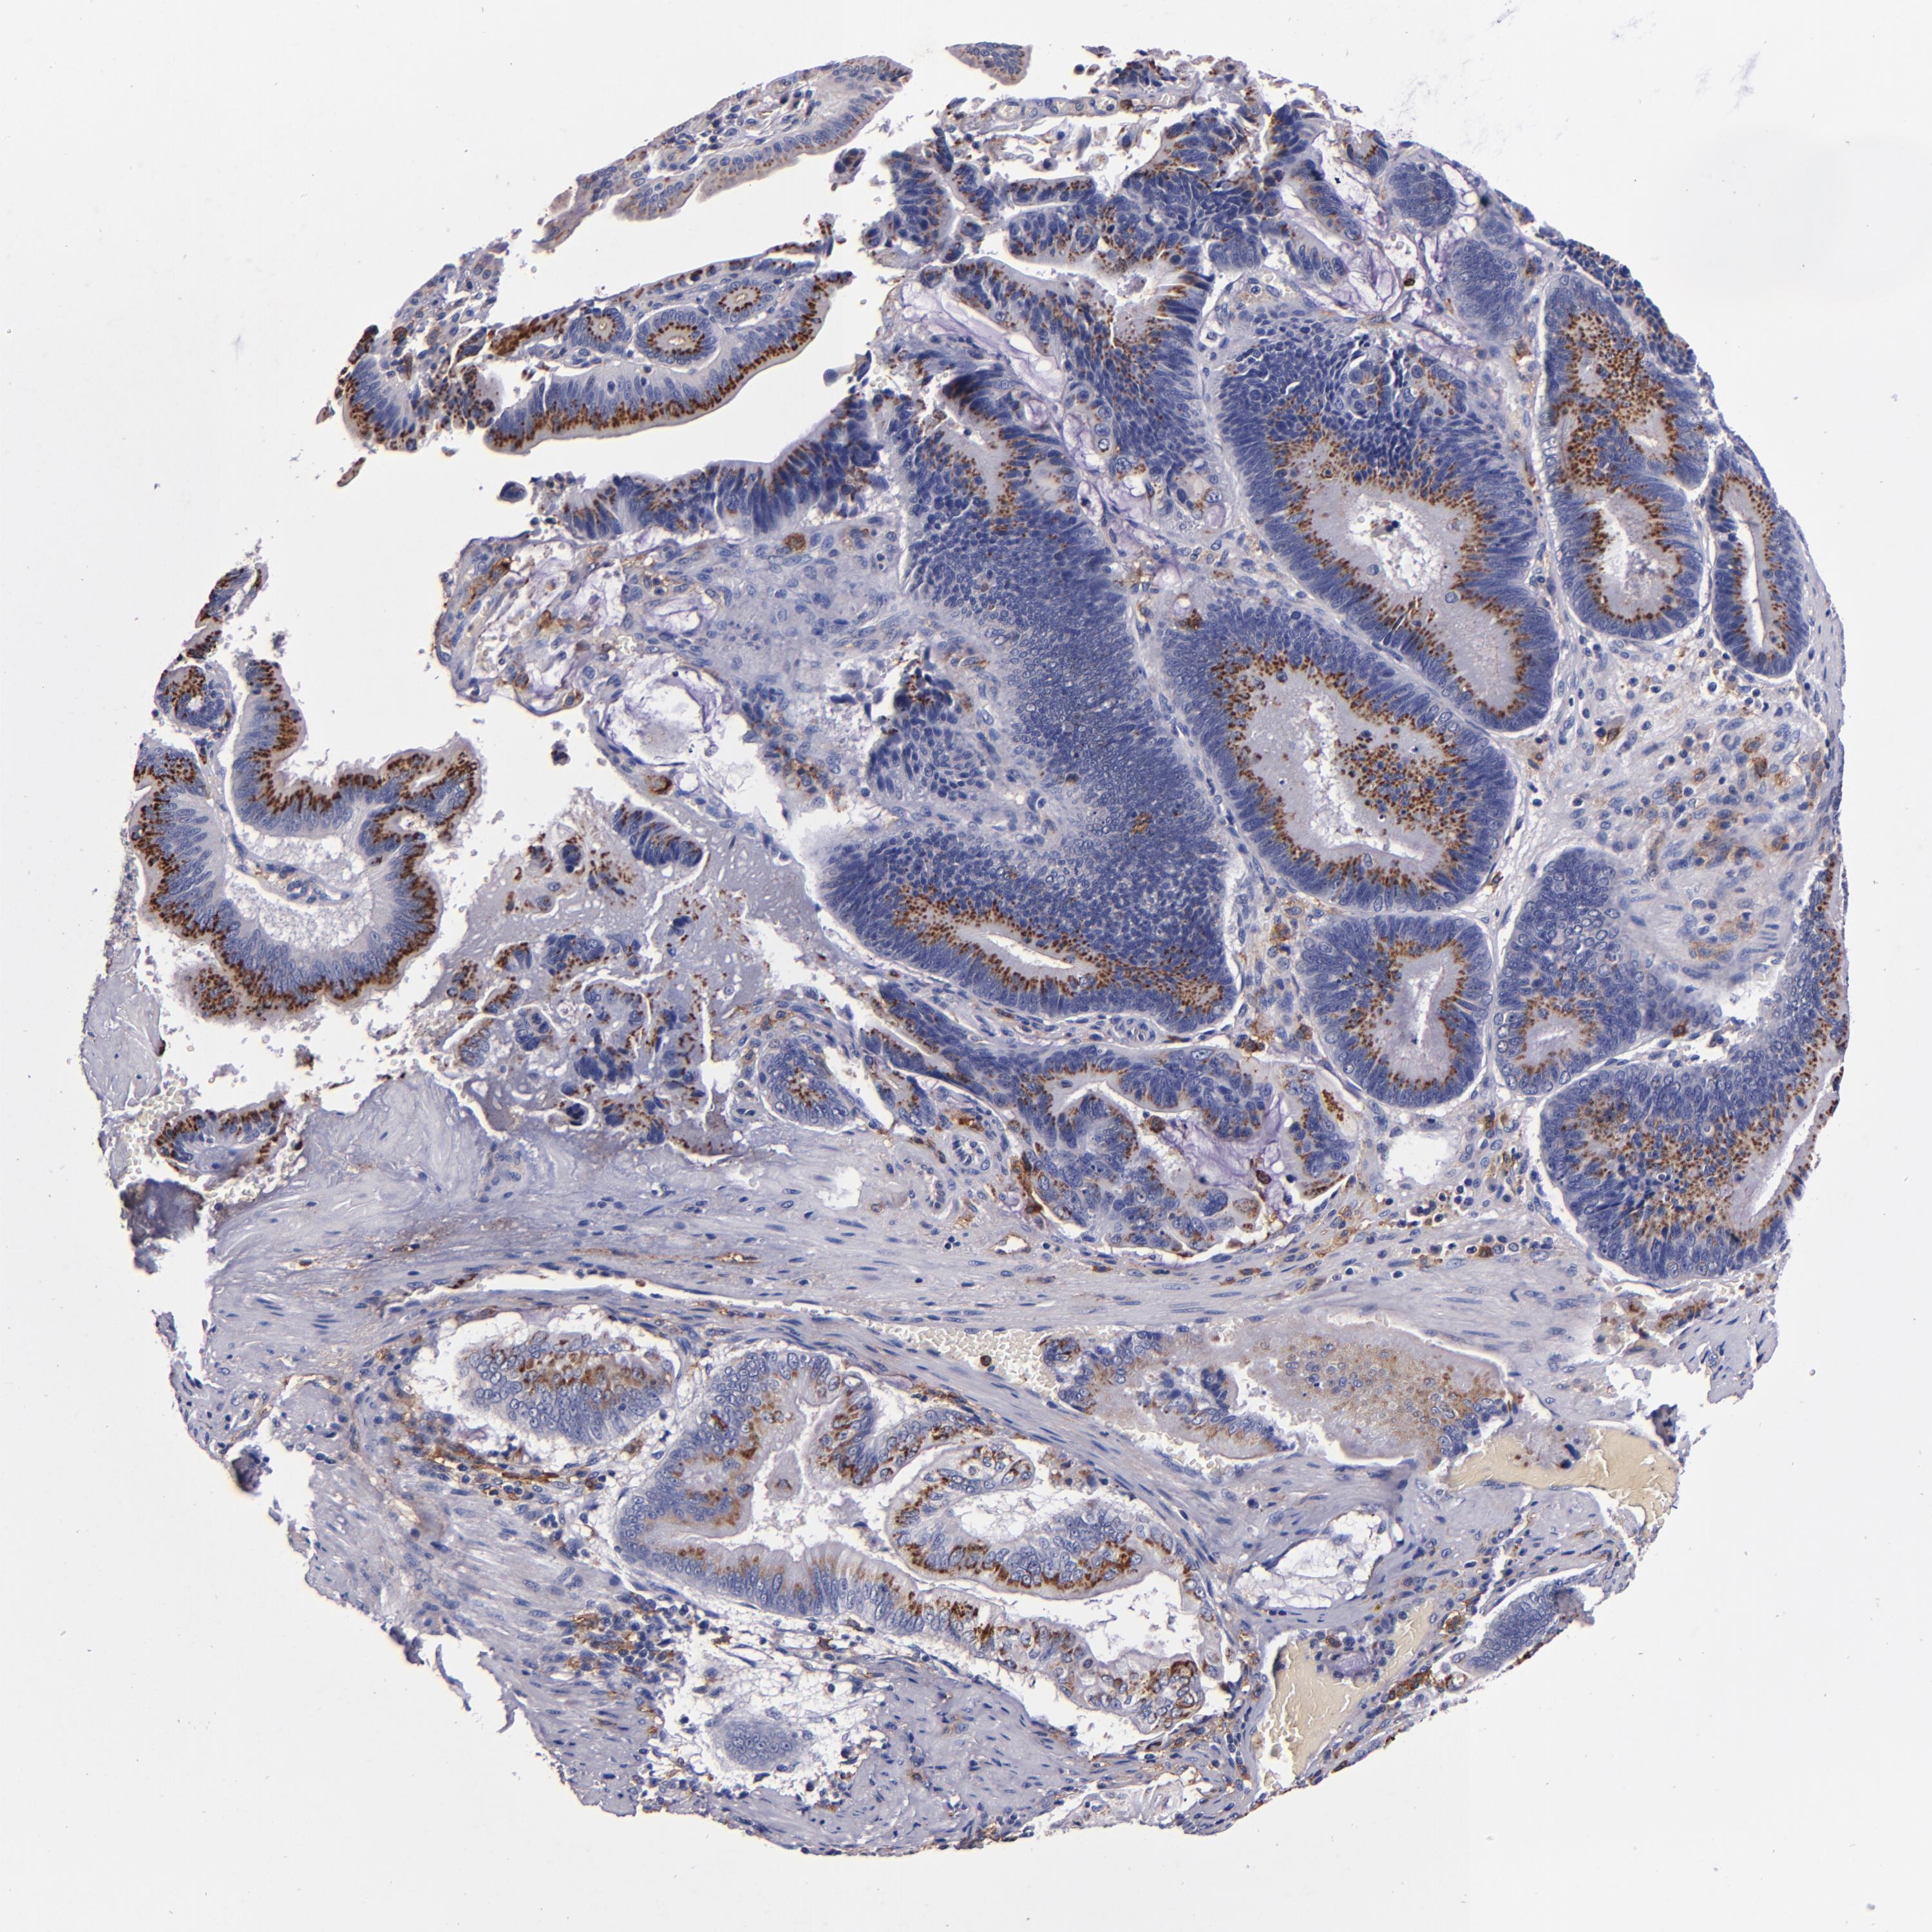

PANCREATIC CANCER - Protein expressioni

A mouse-over function shows sample information and annotation data. Click on an image to view it in a full screen mode. Samples can be filtered based on level of antibody staining by selecting one or several of the following categories: high, medium, low and not detected. The assay and annotation is described here.

Note that samples used for immunohistochemistry by the Human Protein Atlas do not correspond to samples in the TCGA dataset.

Antibody stainingi

Antibody staining in the annotated cell types in the current human tissue is reported as not detected, low, medium, or high, based on conventional immunohistochemistry profiling in selected tissues. This score is based on the combination of the staining intensity and fraction of stained cells.

Each image is clickable and will lead to virtual microscopy that enables deeper exploration of all samples and also displays staining intensity scores, fraction scores and subcellular localization as well as patient and tissue information for each sample.

Antibody HPA054437

Antibody HPA058511

Antibody CAB002776

Antibody CAB015122

Adenocarcinoma, NOS

Adenocarcinoma, metastatic, NOS